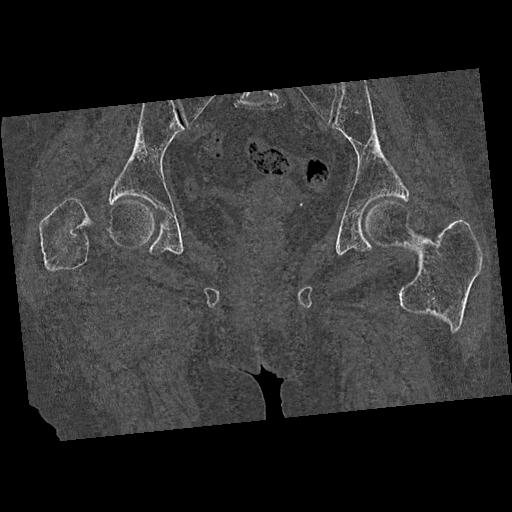

46666 1/28 両股正面+軸と 1/26 右手関節 2R 76歳女性 右転子部骨折